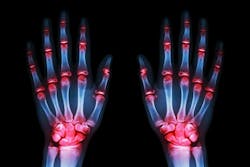

Rheumatoid arthritis (RA), in particular, is one of the most common and debilitating autoimmune diseases, affecting about 1.3 million Americans.6 Timely and accurate diagnosis is critical, as early treatment can prevent irreversible joint damage and improve long-term outcomes. However, diagnosing RA remains complex since symptoms overlap with many other conditions and biomarkers are not always clear-cut, though advances in laboratory technology are beginning to close these gaps and help clinicians detect RA earlier and with greater accuracy.

More than 15 million Americans live with one or more autoimmune diseases, 7 but up to 76% of autoimmune patients report at least one misdiagnosis.8 Diagnosing RA can be particularly challenging because the symptoms mimic many other conditions, and clinicians who are not specialists in identifying autoimmune diseases may not spot the signs early. RA symptoms, such as fatigue, joint stiffness, and pain, are often nonspecific and can resemble other inflammatory or autoimmune conditions. For RA specifically, one recent study found that 48.3% of patients with RA were misdiagnosed before presentation to a rheumatologist.9 Additionally, up to 20% of RA patients — likely even more, depending on the study — are seronegative, meaning that they are not going to test positive for the most relevant diagnostic markers.